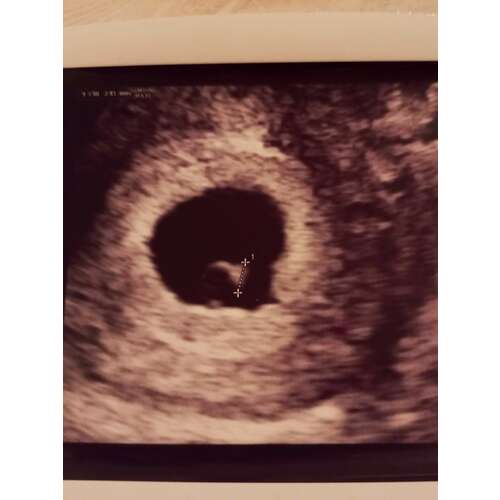

Wij hebben gisteren ook onze eerste echo gehad. Ik dacht bijna 7 weken te zijn maar daar is ook de vrucht te klein voor, 2.2mm dus heeft de echoscopiste ons terug gezet naar rond de 6 weken. Zagen wel het hartje knipperen maar was nog te klein om goed te kunnen beoordelen. Misschien valt het bij jou dus ook mee. Het hartje is pas net aangemaakt sinds een aantal dagen dus zegt nog niet zoveel. Wacht rustig af tot de volgende echo, hoe rustiger jij bent, hoe rustiger jouw baby kan groeien. Sterkte!

De hoop is gebaseerd op het feit dat ik maar 1 volledige cyclus heb gehad voor we de zwangerschap ontdekte. Die was precies volgens de pil 28 dagen. Dit kan betekenen dat mijn ovulatie en dus bevruchting later was dan de standaard berekening. Ook omdat we maar 1 test gedaan hebben, die meteen positief was, weten we niet of dat ik bijvoorbeeld 2 dagen daarvoor nog negatief getest zou hebben. In ons meest gunstige geval was ik op onze testdag 17 september net 4 weken zwanger. 🍀 Dan zou ik afgelopen maandag met de echo 5+3 geweest zijn. Dan zou 2,5 mm wat gemeten is goed zijn, en dan zou dat ook het matig kloppende hartje verklaren omdat deze pas net is gaan kloppen. Als we de echo 1 dag eerder hadden gehad was er dan wellicht niet eens een hartje waargenomen. ❤️ Echter heb ik dan wel een hele late ovulatie gehad en dat komt niet vaak voor.

Daarbij geeft ze aan dat op zo'n vroege periode het heel lastig is om correct te meten. Het is echt millimeter werk. Dat is meteen ook de reden waarom de echo echt niet eerder kan dan volgende woensdag; anders worden er wellicht verkeerde conclusies getrokken. (Daarom wordt ook pas met de latere echo de termijn bepaald want dan gaat het om centimeters en geen millimeters).